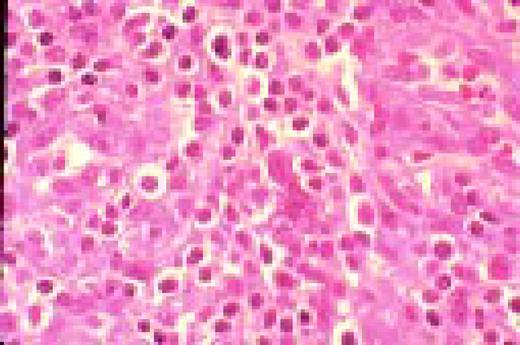

Slide L50

Kaposi sarcoma, lymph node section, H&E. This lymph node from a patient with AIDS has been virtually completely infiltrated with Kaposi sarcoma.FIG50